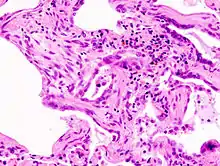

| End-stage pulmonary fibrosis of unknown origin, taken from an autopsy | |

Prolonged ILD may result in pulmonary fibrosis, but this is not always the case. Idiopathic pulmonary fibrosis is interstitial lung disease for which no obvious cause can be identified (idiopathic) and is associated with typical findings both radiographic (basal and pleural-based fibrosis with honeycombing) and pathologic (temporally and spatially heterogeneous fibrosis, histopathologic honeycombing, and fibroblastic foci).

A lung biopsy is required if the clinical history and imaging are not clearly suggestive of a specific diagnosis or malignancy cannot otherwise be ruled out. In cases where a lung biopsy is indicated, a trans-bronchial biopsy is usually unhelpful, and a surgical lung biopsy is often required.[9]